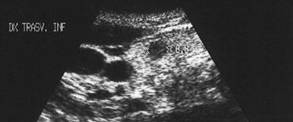

Lob drept, proiectie trasversala si longitudinala.

Femeie de 34 ani. Cunoscute cu hipertiroidism in

cadrul maladiei Graves.

Nodul paraistmic anterior dr. de 11x20x19mm (2 cc), cu margini nedefinite prin

absenta haloului periferic, neomogene, hipoecogen, care deformeaza conturul anterior

al glandei.

Examen citologic: carcinom papilar. Confirmare histologica (carcinom papilar multifocal cu metastaze linfonodale).